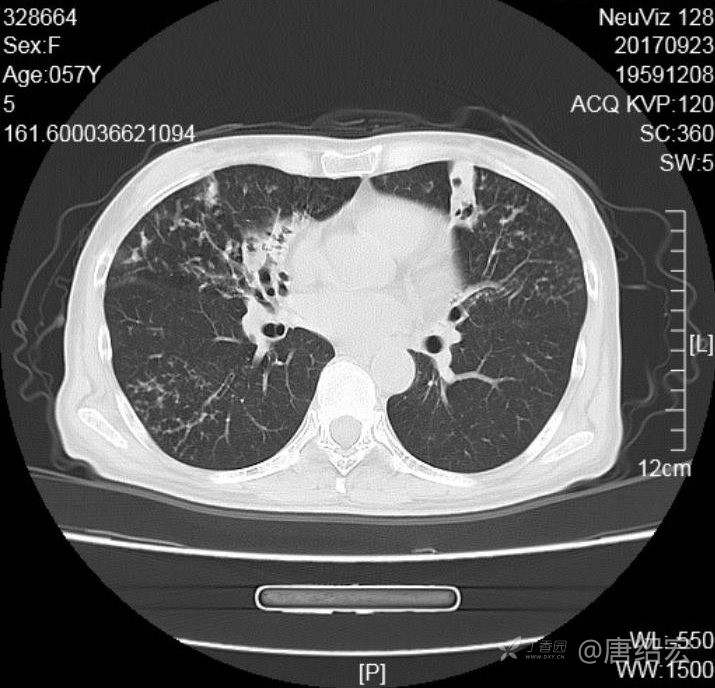

中年女性满肺树芽征还有支气管扩张,考虑什么疾病?

女,57岁,

主诉:发热、咳嗽、咯黄痰,胸闷3天入院。